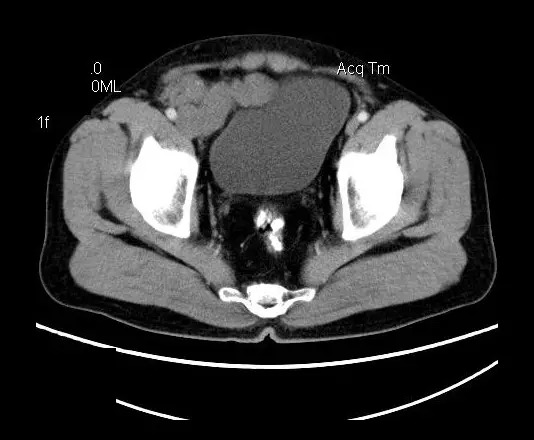

男,50岁,发现盆腔包块一月,无明显触痛,不伴发热。

盆腔右前侧及邻近腹股沟区可见多发大小不等的聚集生长的结节影,病灶呈软组织密度,边缘尚规整,分界尚清,增强扫描可见不均匀强化。膀胱局部受压,盆腔未见明显肿大淋巴结影。

“盆腔”多发性神经鞘瘤